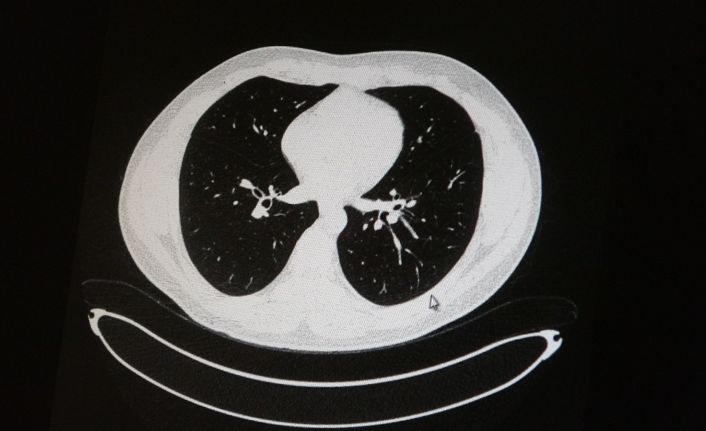

Elazığ’da öksürük, halsizlik, yorgunluk ve çabuk yorulma gibi şikayetlerle hastaneye başvuran ve korona virüs tespit edilen 2 genç hastadan aşısız olanının tomografi sonuçlarında virüsün akciğerlerde zatürreye sebebiyet verdiği görüldü. Aynı şekilde aşı olup korona virüs hastalığına yakalanan bir başka genç hastanın bilgisayarlı akciğer tomografisinde akciğerinde herhangi bir sorunun olmadığı belirlendi.

Medical Park Elazığ Hastanesi Göğüs Hastalıkları Uzmanı Dr. Cebrail Azar, geçtiğimiz yıla oranla yoğun bakımda yatan hastaların yaş ortalamasının 65’ten 35’lere kadar düştüğüne dikkat çekti. Genç olduğu halde aşı olmayanlarda hastalığın ağır seyrettiğini ifade eden Uzm. Dr. Azar, "Ben gencim, benim bağışıklık sistemim kuvvetli" diyen genç bir hastanın akciğerlerinde ciddi lekelenmelerin olduğunu ve korona virüs zatürresi olduğunu gördüklerini belitti. Uzm. Dr. Azar, aynı şekilde aşı olup korona virüs hastalığına yakalanan bir başka genç hastanın akciğer tomografisinde akciğerde herhangi bir sorunun olmadığını ve hastanın durumunun iyi olduğunu gözlemlediklerini kaydetti. Uzm. Dr. Azar, sürekli şahit oldukları "Keşke biz aşı olsaydık" sözünü bir daha duymamak için herkesi aşı olmaya davet etti.